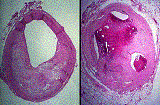

Why EBT?

The only heart test you need

Mammogram of the Heart